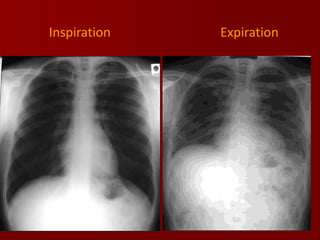

Inspiration:

The volume of air in the hemithorax will affect the

configuration of the heart in relation to cardiac size.

The vascular pattern in the lung fields will be

accentuated with a shallow inspiration.

The level of inspiration can be estimated by

counting ribs.

Visualization of nine posterior ribs, or seven

anterior ribs on an upright PA radiograph projecting

above the diaphragm would indicate a satisfactory

inspiration

Expiration

NOTE - CHANGE IN HEART SIZE AND

VASCULARITY DUE TO EXPIRATION